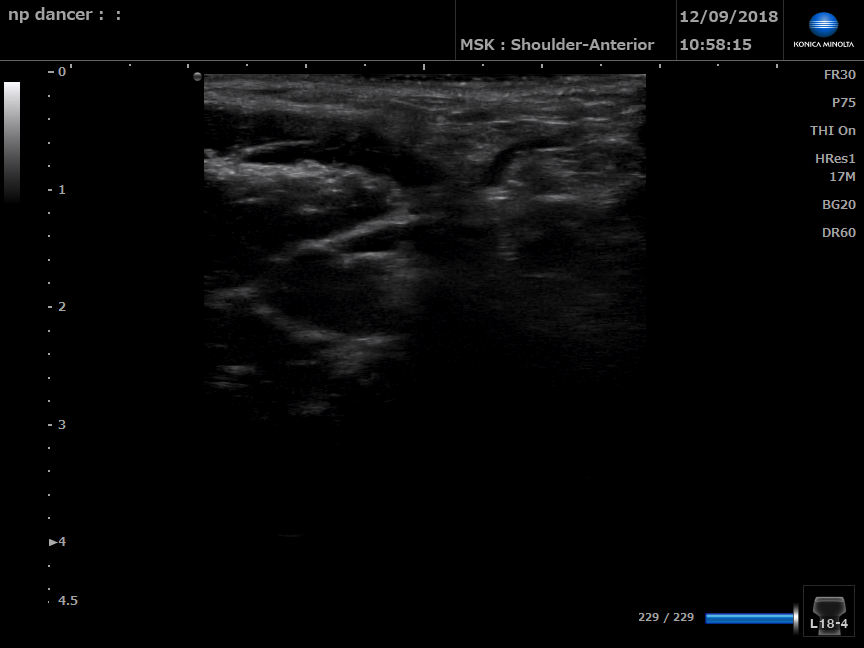

Dancer with pelvic floor dysfunction

B Mode ultrasound of left perineal body